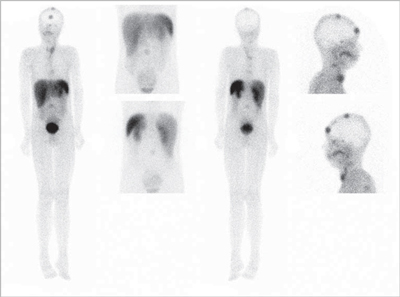

El tumor medular de tiroides es una neoplasia poco frecuente (3-5% de todos los cánceres de tiroides) proveniente de las células C parafoliculares (Figuras 6 y 7). La mayoría ocurre en forma esporádica (70-80% de los casos) pero existen formas familiares (solos o como parte del síndrome NEM 2A y 2B)20. Este tumor metastiza precozmente a los ganglios cervicales (55-75% de los casos), principalmente el compartimiento central del cuello. Metástasis a distancia se encuentran en 10-15% de los pacientes, principalmente mediastino, pulmones, hígado y hueso21 (Figuras 8 y 9). Debido a la producción de calcitonina por las células C, esta hormona es usada como marcador tumoral al diagnóstico y durante el seguimiento. La resección quir úrgica completa (tiroidectomía total y disección cervical amplia) es la únicaforma de curación. A pesar de la agresividad de este tratamiento, 40% de los pacientes operados mantienen niveles de calcitonina medibles y otro 10% inicialmente negativo, recurrirá en el tiempo2. Por esta razón, la localización de cualquier cúmulo tumoral existente mediante imágenes es de extrema importancia. Los criterios usados en imágenes diagnósticas para el tumor primario son similares a los usados en el cáncer diferenciado de tiroides, sin embargo, la localización de adenopatías y metástasis a distancia es generalmente difícil22. Convencionalmente se ha usado ecografía, tomografía computada y cintigrafía (In111-pentatreotide, Tc99m-DMSA- V y Tc99m-MIBI) para evaluar pacientes con enfermedad recurrente. Tc99m(V)-DMSA (ácido dimercaptosuccínico pentavalente) es un marcador tumoral inespecífico. El mecanismo de captación es sólo parcialmente conocido y tendría relación con la presencia de grupos fosfatos y el pH del medio. Su uso en esta enfermedad fue descrito por primera vez en 1984 por Ohta23. La sensibilidad reportada de la cintigrafía con DMSA-V se encuentra entre 50-80% y su uso combinado con In111- pentatreotide alcanza 86%24. F18-FDOPA es un aminoácido (dihidroxifenilalanina) marcado con Flúor18 usado originalmente para el estudio de pacientes con enfermedad de Parkinson. Los tumores neuroendocrinos pueden captar y decarboxilar p recursores de aminoácidos tales como la DOPA y ser visualizados con PETFDOPA. Las series reportan sensibilidades entre 44 y 90% para este método2. Desafortunadamente para la síntesis de F18-FDOPA se requiere de blancos especiales en el ciclotrón (diferentes a los usados para la producción de FDG) y de módulos de síntesis dedicados, lo que hace que este radiofármaco aún no esté disponible en nuestro medio. Si bien el 85% de los tumores medulares de tiroides expresan algún tipo de receptores de somatostatina y 75% expresan los tipos 2,3 ó 5 (que son los afines por octreotide), el subtipo 2 es expresado sólo en 43%25, que es el blanco principal de los análogos disponible para imagen y terapia. La afinidad de estas moléculas por los subtipos 3 y 5 es típicamente menor. Esto explica la variabilidad de resultados en la literatura en relación con la sensibilidad tanto de la cintigrafía con In111-pentatreotide (Octreoscan) como para el PET con derivados de la somatostatina para la detección de esta neoplasia. Las series publicadas con In111-pentatreotide reportan sensibilidades entre 50-75% para cáncer medular de tiroides y sugieren que este método es mejorpara metástasis ganglionares en el cuello o mediastino que para metástasis a distancia2. Estudios con PET y análogos de somatostatina son escasos para esta enfermedad. La limitada información disponible sugiere que la sensibilidad de PET-análogos de somatotatina es inferior al PET-FDOPA en cáncer medular de tiroides tanto a nivel de paciente como de lesión y similar a los resultados de estudios realizados con PET-FDG. En el trabajo retrospectivo de Conry et al2, se estudiaron 18 pacientes con recidiva de cáncer medular de tiroides a los que se le realizó PET con Ga68-DOTATATE y F18-FDG. La sensibilidad encontrada por paciente fue 72% para DOTATATE y 78% para FDG. FDG encontró 28 metástasis mientras que DOTATATE 23. Treglia et al26 recientemente publicó una serie prospectiva de 18 pacientes con recurrencia de cáncer medular de tiroides estudiados PET y Ga68-análogos de somatostatina, F18-FDOPA y F18-FDG. En este trabajo la sensibilidad por paciente fue 72% para FDOPA, 33% para análogos de somatostatina y 17% para FDG. A nivel de lesiones la sensibilidad fue: 85% para FDOPA, 20% para análogos de somatostatina y 28% para FDG.